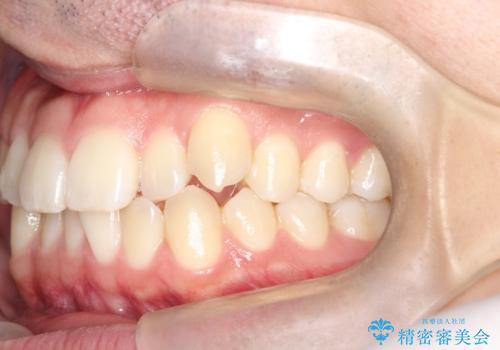

- 八重歯が気になるとのことでご来院されました。お口の中を確認すると、上の前歯がスペース不足で押し出され、少し前に出ている状態でした。抜歯せずに整えるため、奥歯を少しずつ後ろに動かしながら(遠心移動)、歯と歯の間をわずかに削るIPRを行ってスペースを作ることにしました。また、上下の噛み合わせを整えるために2級ゴム(エラスティック)を使用する方針を立てました。

マウスピースを段階的に交換しながら、奥歯を少しずつ後ろへ動かし、八重歯がきれいに並ぶよう調整しました。前歯の突出感を抑えるためにIPRを行い、スムーズに配列。さらに、2級ゴムを活用して噛み合わせも改善しました。治療後は、自然な歯並びになり、笑顔に自信が持てるようになったと喜んでいただきました。